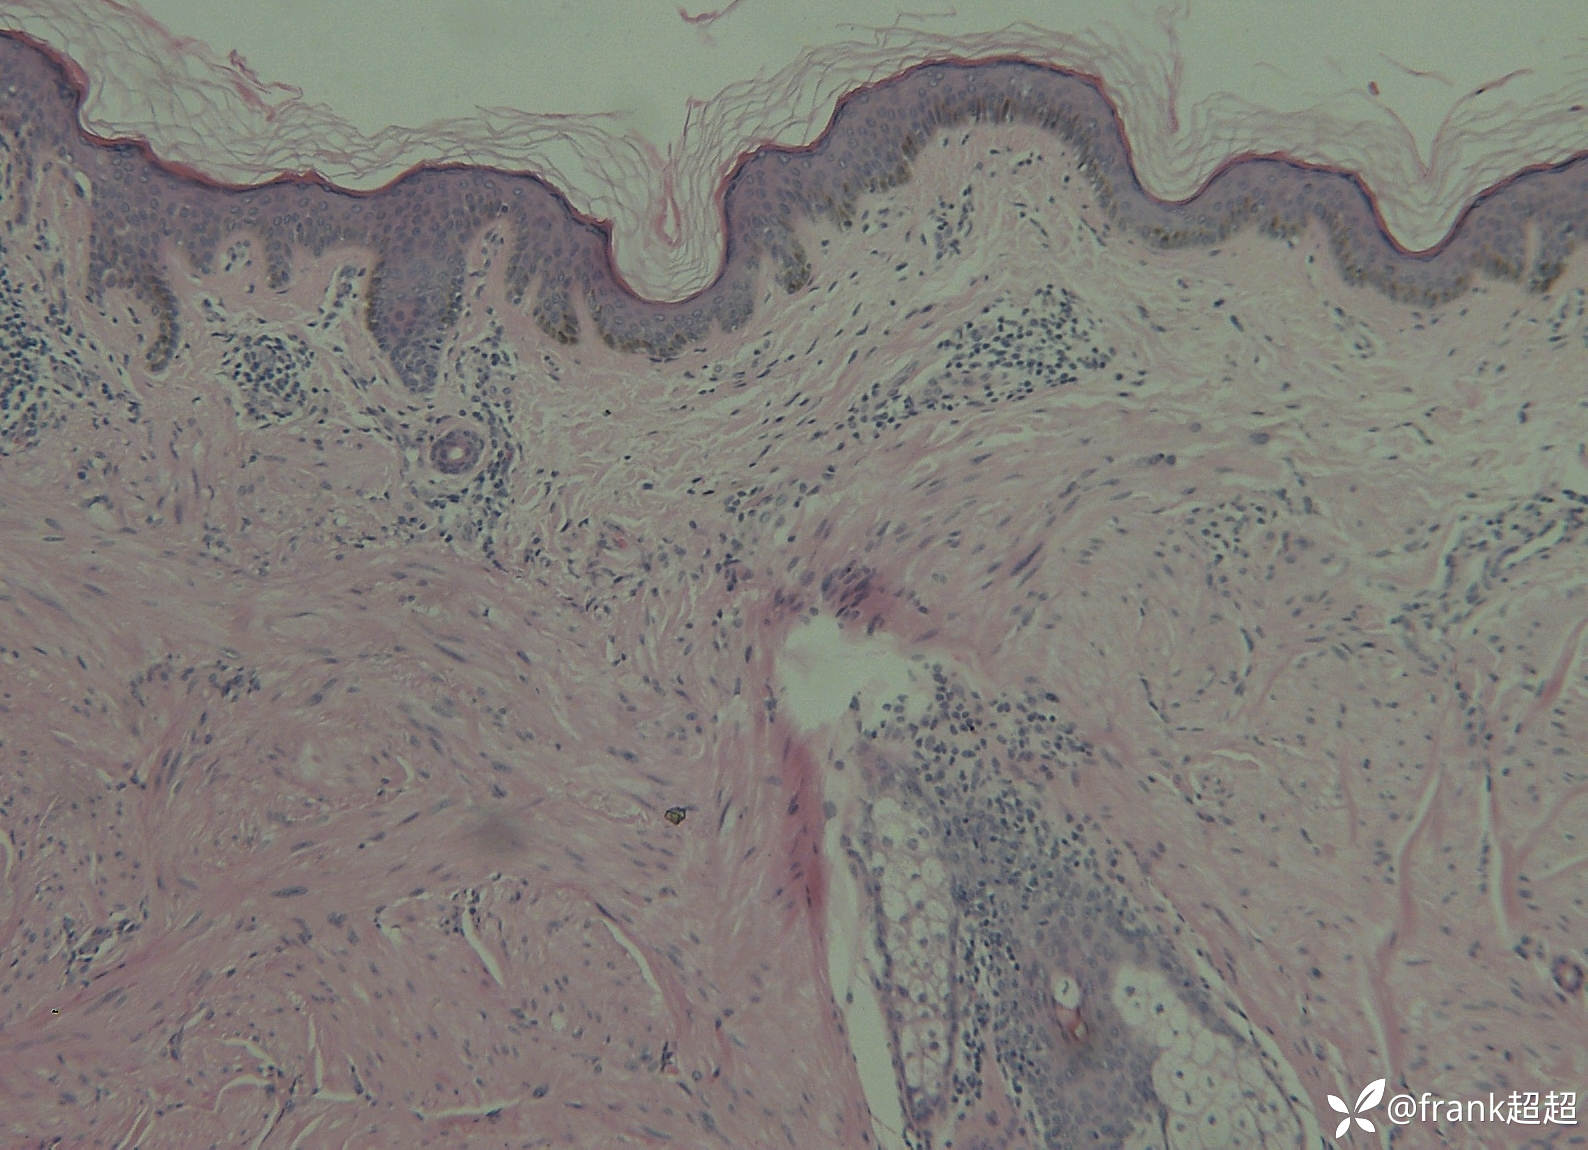

病理结果:真皮深层可见一大的肿瘤细胞团块,团块与周围组织界限清楚但无包膜,肿瘤组织由大量肌纤维组成,其细胞核大多呈两头钝。